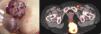

Una mujer de 57 años, sin antecedentes médicos de interés, consultó por 2 grandes masas acrómicas, colindantes, una de ellas ulcerada, localizadas en la región sacra y la nalga izquierda. A la exploración presentaba 2 tumoraciones eritematosas de unos 6cm de diámetro, con una zona central erosiva-costrosa. La resonancia magnética pélvica mostraba 2 grandes masas sólidas, heterogéneas de origen dérmico en la región sacra y paramedial izquierda, sin alteraciones musculares ni óseas secundarias. La biopsia cutánea fue de melanoma de localización dérmica y subcutánea, sin afectación epidérmica. El PET/TC mostró 2 masas en la región glútea izquierda, la más craneal excrecente de aproximadamente 6,4×3,2cm con SUVmáx 28,6, la otra contacta con el pliegue interglúteo de aproximadamente 5,0×7,3cm con SUVmáx 30,3 sugestivas de malignidad. Además, se observan adenopatías pélvicas localizadas en la región inguinal izquierda sugestivas de malignidad (fig. 1).